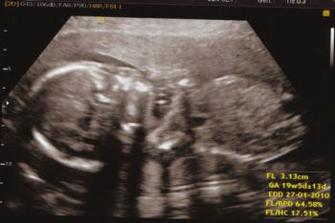

Pondělní ultrazvuk dopadl výborně. Miminko má všechno, co má mít a je zdravé.

A vím, co čekáme....naše miminko má pindíka. 🙂

Ultrazvuku se zúčastnil i tatínek, ale chudák toho moc neviděl. Prcek měl tvářičku zabořenou do placenty a ručičky měl v klíně, nožičky skrčené tak, že nebylo vidět, jestli je to holčička nebo chlapeček. Možná bude v porodnici překvapení.🙂)

18. ledna - ultrazvuk a odhad váhy miminka - malý váží kolem 3 400 g. Všechno ostatní v pořádku.